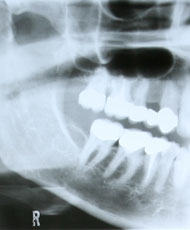

Endodontie (Wurzelkanalbehandlung)

Mit ihren Wurzeln sind unsere Zähne fest im Kiefer verankert. Was passiert jedoch, wenn eine Zahnentzündung so weit voranschreitet, dass die Zahnwurzel abstirbt oder wenn durch einen Unfall ein Teil des Zahnes abbricht?

Solange die Zahnwurzeln und der umgebende Knochen festen Halt geben, empfiehlt es sich, den Zahn oder die Zahnwurzel als Stützpfeiler zu erhalten. Besonders dann, wenn durch eine Extraktion die nebenstehenden Zähne als Pfeiler für eine Brücke beschliffen werden müssten.

Damit der abgestorbene Zahnnerv keine Kiefer-Knochenentzündungen und Schmerzen hervorruft, müssen sämtliche Bakterien und Gewebereste maschinell oder von Hand aus den Wurzelkanälen entfernt werden. Die Kanäle werden anschließend mit speziellem Wurzelfüllmaterialien dicht verschlossen. Die Verfahren die dabei angewendet werden bezeichnet man in der Zahnmedizin als laterale und vertikale Kondensation und thermische Obturation. Dabei wird das eingebrachte Material seitlich, vertikal und unter Wärmezufuhr verdichtet. So wird eine optimale Versiegelung der Kanäle erreicht.

Je nach Größe des begleitenden Zahndefekts ist die anschließende Versorgung mit einer Krone und eventuell einer Stiftversorgung erforderlich.